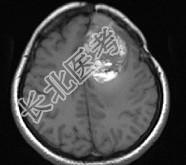

- 单项选择题女,39岁, 三年前因左额部胶质瘤手术治疗,最近出现头痛, 并抽搐大发作1次,请根据所提供图像, 诊断最有可能是 ( )

A、(左额叶)脑脓肿

B、(左额叶)脑出血

C、(左额叶)星形细胞瘤Ⅱ~Ⅲ级

D、(左额叶)脑转移瘤

E、(左额叶)放射性脑炎